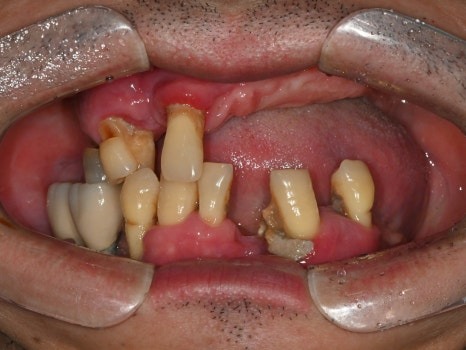

치료 전 파노라마

치료 전 사진

오래 전 임플란트 치료를 하였지만

염증으로 인해 모두 빠져버린 상황에서

오른쪽 하나만 닿는 어금니로 식사를 하고 계시던 중,

위쪽 치아마저 아파지면서

식사가 아예 불가능하게 되었다고 하셨습니다.

남은 치아는 모두 발치해야 하는 상황,